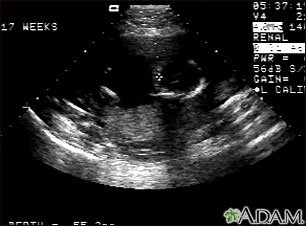

Ultrasonido normal a las 17 semanas de gestación. El cerebro y el sistema nervioso comienzan a desarrollarse con prontitud en la vida del feto. Al realizar un ultrasonido, el técnico por lo general busca la presencia de los ventrículos cerebrales, los cuales son los espacios llenos de líquido en el interior del cerebro. En este ultrasonido los ventrículos pueden observarse en la parte superior derecha en forma de líneas finas que se extienden a través del cráneo. La cruz apunta hacia la parte frontal del cráneo y a su derecha se pueden observar las líneas de los ventrículos.